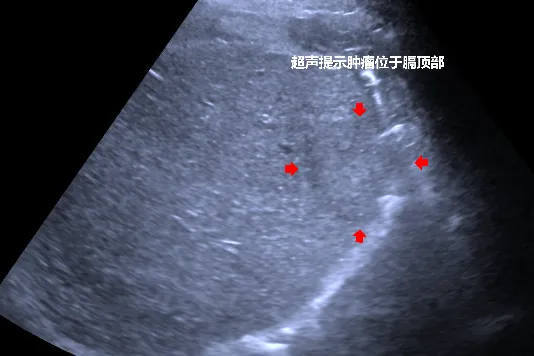

来到眉县常兴中心卫生院疼痛科后,于军辉书记为其进行了详细的体格检查与影像学评估,明确诊断为退行性膝关节炎。为他制定了“关节腔注射+针灸理疗+康复训练”的综合治疗方案。经过两周的系统治疗,何先生的疼痛症状得到了显著缓解,下肢活动功能也基本恢复。在后续的随访中,医护人员持续为他提供居家康复指导,帮助他巩固疗效、预防复发。